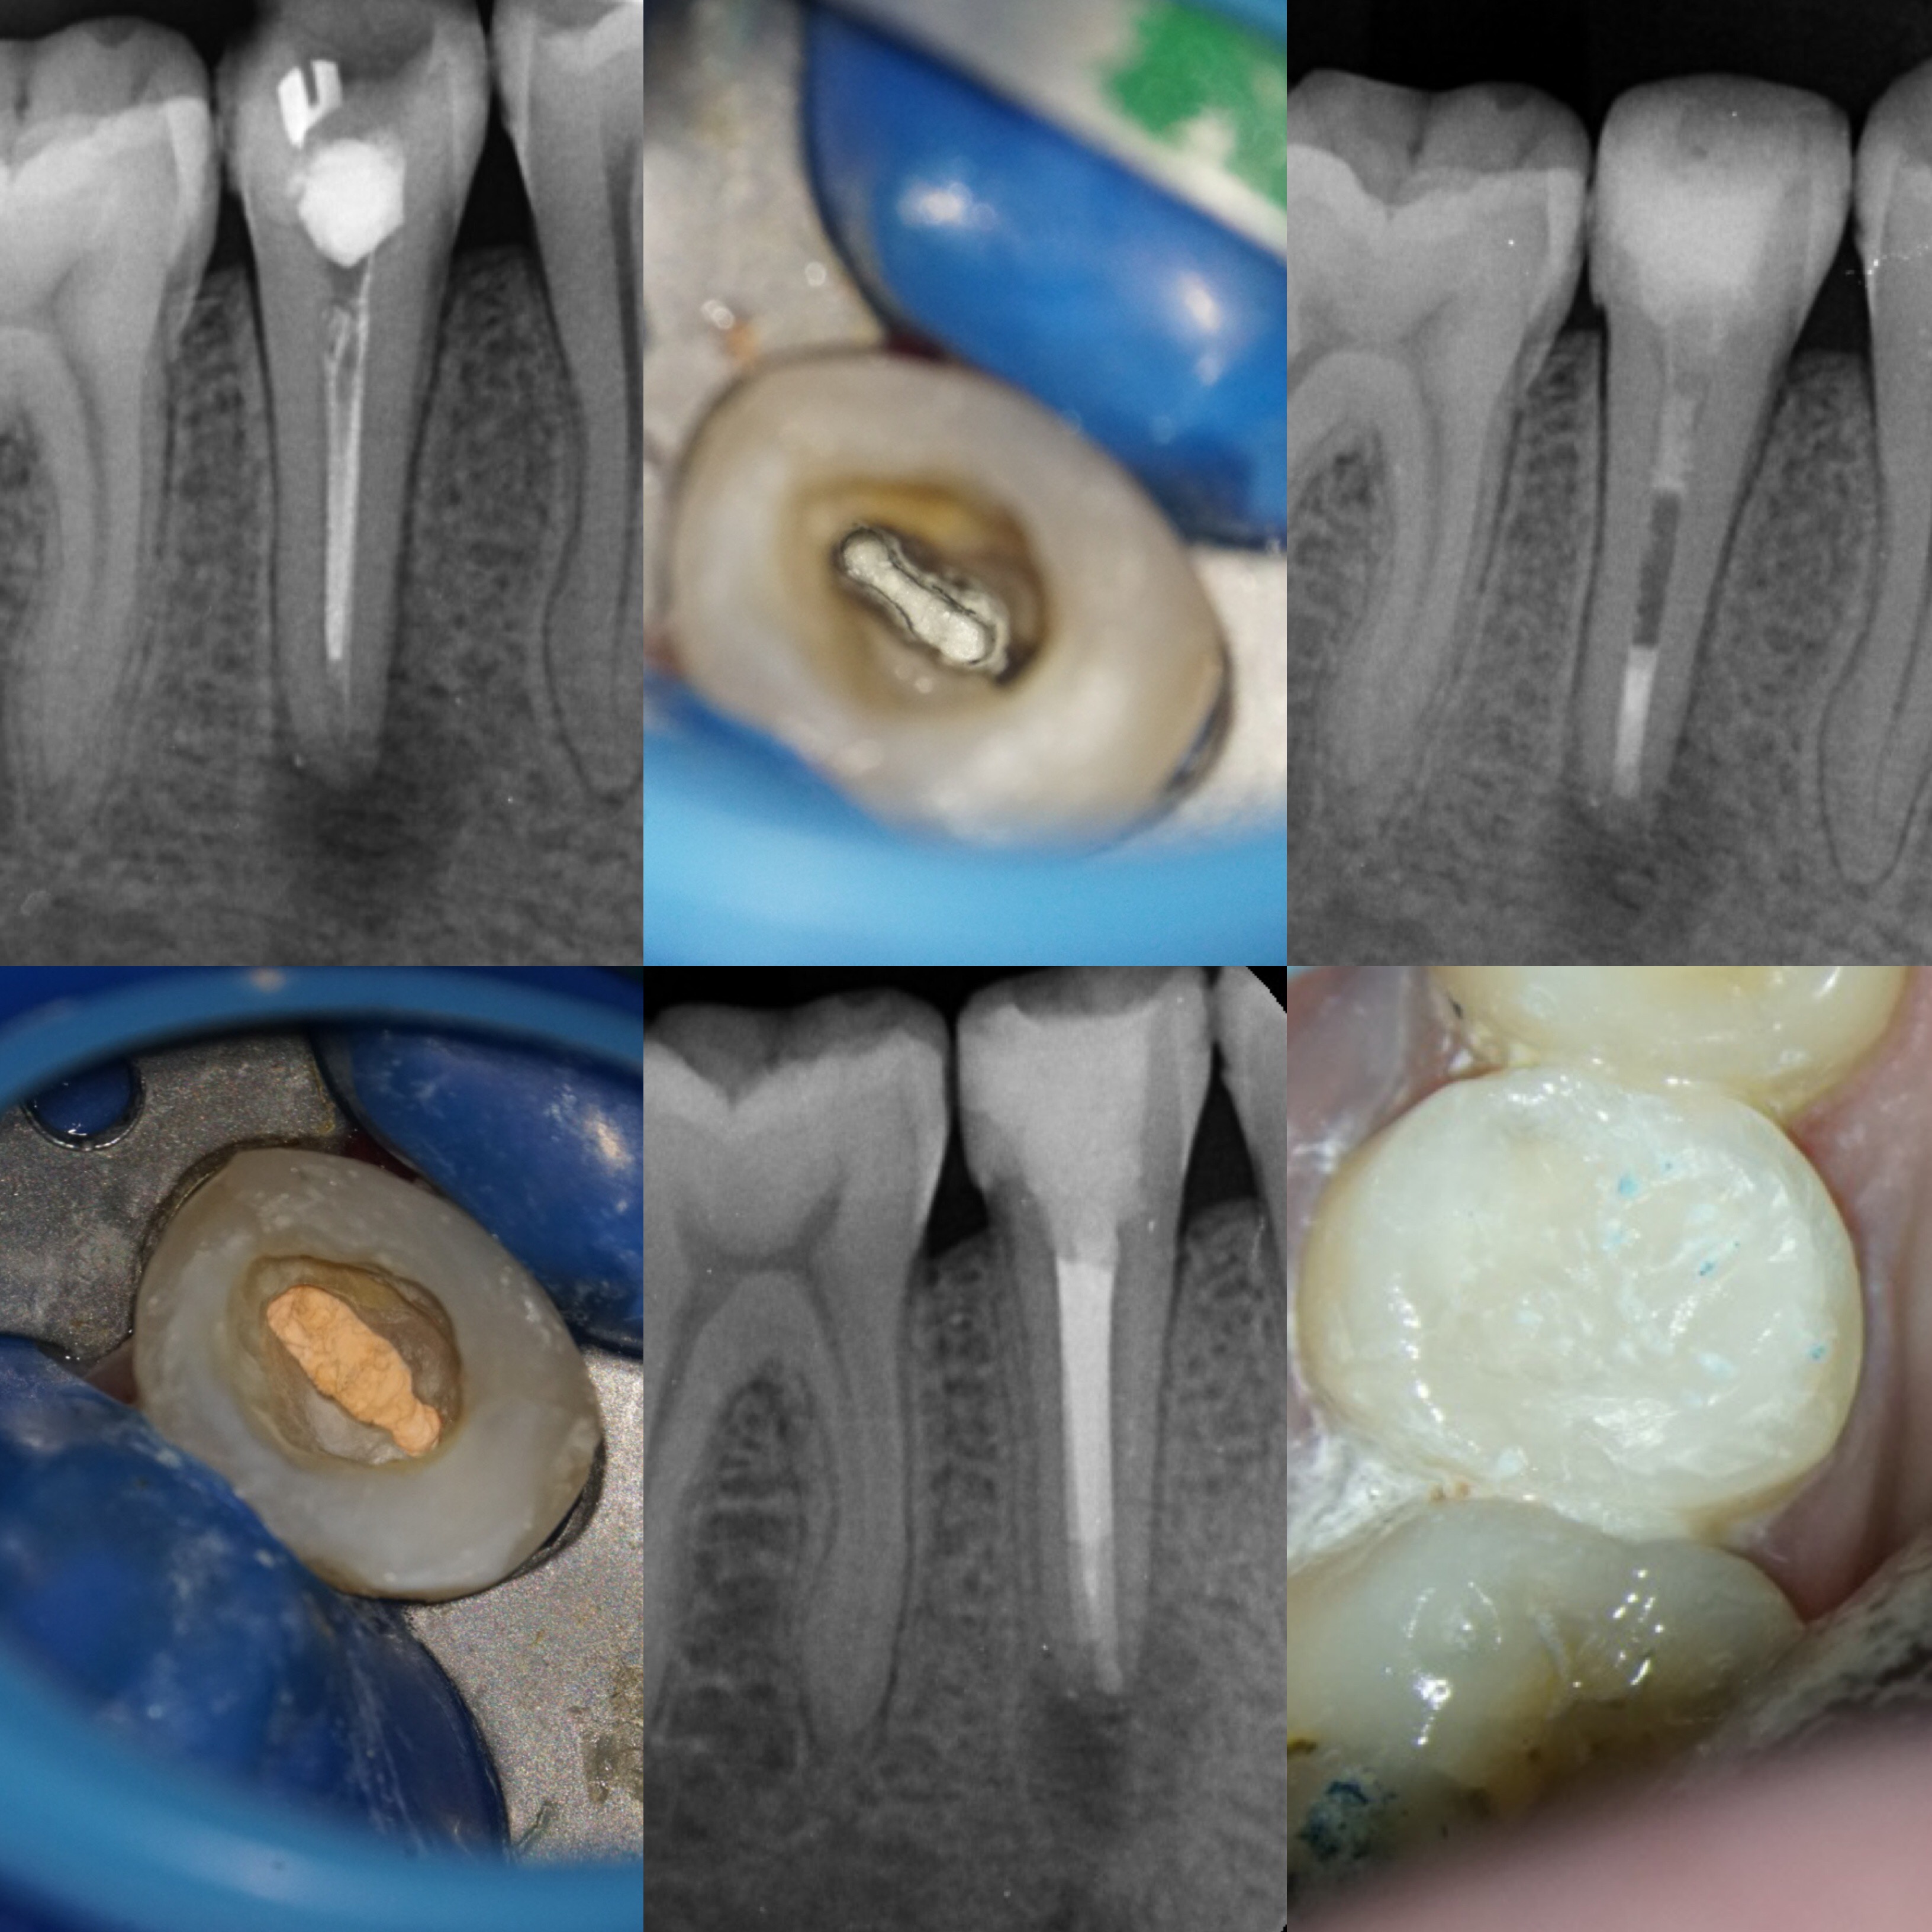

Klinik Vakalarla Kanal Tedavili Posterior Dişlerin Estetik Restorasyonu

"Klinik Vakalarla Kanal Tedavili Posterior Dişlerin Estetik Restorasyonu" başlıklı uygulamalı eğitimin yeni programı 7 Nisan 2018 tarihinde İstanbul Kadıköy'de gerçekleştirilecek.

“Klinik Vakalarla Kanal Tedavili Posterior Dişlerin Estetik Restorasyonu” eğitimi konu ilgili çalışmaları ilgiyle takip edilen Yrd. Doç. Dr. Bora Korkut ve Dr. Toygan Bora tarafından verilecek. GC Türkiye tarafından desteklenen uygulamalı eğitim, 7 Nisan tarihinde İstanbul Kadıköy’de gerçekleştirilecek.

Bu eğitimde diş kliniğinde en çok karşılaşılan problemlerden biri olan kanal tedavisi görmüş posterior dişlerde doğru restorasyon seçimi ve uygulamaları ile ilgili klinik vakalar üzerinden detaylı anlatım yapılacaktır.

Bir kanal tedavisi uzmanı ve bir restoratif diş tedavisi uzmanının eşzamanlı anlatım yapacağı eğitimin teorik bölümünde, kanal tedavisi ve üst restorasyonun tedavi başarısını ayrı ayrı nasıl, ne ölçüde etkilediği ve bu iki işlemin birbiri ile olan ilişkisi detaylı olarak ortaya konulacaktır.

Posterior dişlerde kanal tedavisi sonrası kalan diş dokusuna göre hangi tip restorasyonun tercih edilmesi gerektiği ve uygulaması klinik vakalar üzerinden tartışılarak anlatılacaktır. Katılımcılara ayrıca posterior dişlerde endodontik tedavide başarı kriterleri ve posterior direkt estetik kompozit tabakalaması ile ilgili detaylı bilgi verilecektir.

Pratik eğitim ise iki bölümden oluşacak olup birinci bölümde kanal tedavisi uzmanı Dr. Toygan Bora tarafından tüm detaylarıyla bir posterior dişe kanal tedavisi uygulaması yapılacaktır. İkinci bölümde ise restoratif diş tedavisi uzmanı Yrd. Doç. Dr. Bora Korkut tarafından tüm katılımcılarla senkronize şekilde adım adım bir posterior dişe direkt estetik kompozit tabakalama uygulaması yapılacaktır.